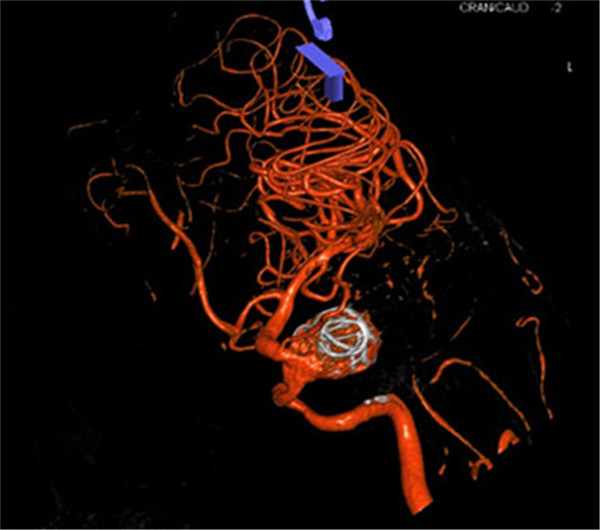

患者是一位70岁的女性,已视物重影1年余,经外院检查确诊为“左侧颈内动脉海绵窦段巨大动脉瘤伴瘤内血栓形成”,医生告知因动脉瘤位于海绵窦内,瘤颈宽约8mm,大小约2.8×2.3×2.2cm,传统手术方法无法完成动脉瘤夹闭或栓塞治疗,同时手术创伤大、风险高。听了医生的话患者不得不放弃手术。

最近,患者因症状加重来到Beat365中国唯一官方网站第一附属医院求治。该院神经外科张高炼主任主持的治疗团队对该病例进行了讨论和分析,因影像学检查显示动脉瘤载瘤动脉明显迂曲且血管直径较细小,覆膜支架系统通过可能较困难且易引起载瘤血管损伤或动脉瘤破裂出血,他们决定利用密网支架技术行颅内巨大动脉瘤封堵技术为患者治疗。新技术的开展经汇报后得到院领导的大力支持,医院为此简化医疗药械申购手续,购买由美国eV3公司生产的Pipeline血流导向装置(密网支架系统),并邀请到中美合作上海德济医院院长宋冬雷教授前来会诊和指导。

手术在气管插管全麻下进行,微导管顺利送到理想位置,由于出现血管痉挛,立即行解痉处理,好转后置入血流导向装置,由于瘤腔血流速度快,置入弹簧圈支撑支架,并缓慢释放装置,经造影显示动脉瘤消失,载瘤动脉通畅。手术过程顺利,术后患者神志清醒,言语切题,视力无异常改变,四肢活动正常,患者已缓慢下床活动,手术获得圆满成功。手术当日有来自广西区内多家医院神经外科主任的现场观摩与交流。

密网支架置入